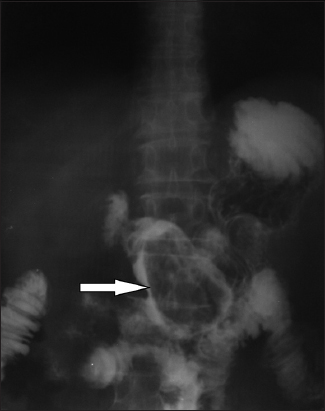

Radiological imaging also plays a crucial role in the diagnostic approach. Plain X-rays may show air-fluid levels that suggest intestinal obstruction, while barium studies may contribute to the differential diagnosis among intestinal diverticuli, adenomas, malignancies and bezoars (Fig. 1). Unfortunately, these studies are insufficiently accurate and are inappropriate for detailed emergency investigation, or for the preoperative assessment of intestinal perforation or complete obstruction [50]. Undoubtedly, contrast-enhanced computed tomography (CT) scanning is the radiological method of choice, showing high sensitivity (up to 90%) and specificity (up to 60%). Phytobezoars, the most common bezoars, are visualized as round or ovoid masses with air-bubbles and a mottled appearance [51] (Fig. 2). Interestingly, they may appear similar to small bowel feces; the latter are discovered in about 8% of cases with ileus. It should be noted that, on radiological imaging, feces tend to appear in a longer segment and are associated with sharp-margin dilatation compared to bezoars, which tend to slide back and forth intraluminally [52,53].

Figure 1 Abdominal radiography with per os administration of an iodinated contrast medium shows a gastric phytobezoar as a filling defect (arrow)